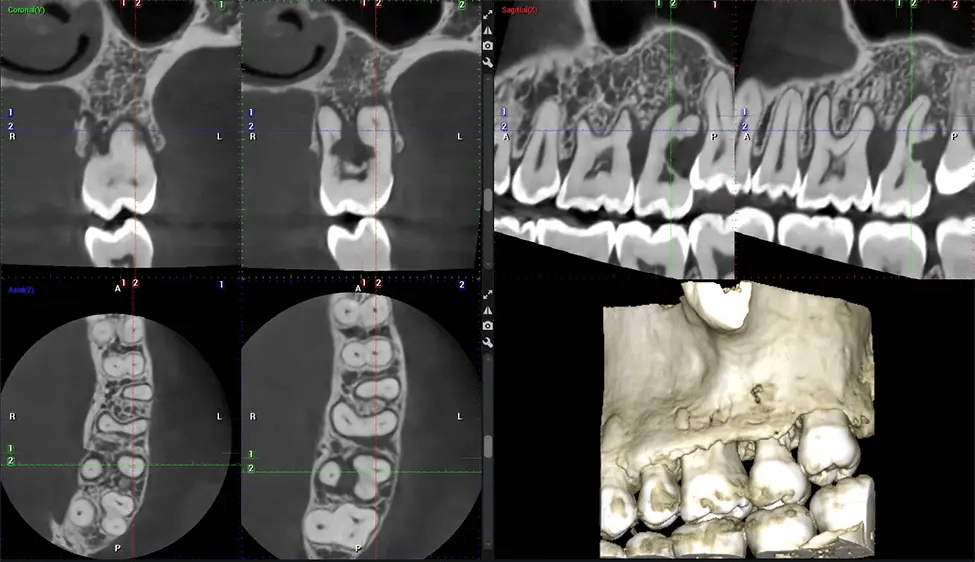

This 3D scan, called cone beam computed tomography, gives your dentist a more complete image of your oral anatomy and disease processes than a traditional X-ray. Unlike conventional X-rays, which capture a 2D image of your mouth from various angles, a 3D scan takes multiple digital X-rays for one image. It provides a complete view of your jaw, teeth, nerves, and soft tissues. This enhanced view allows dentists to detect minor issues not visible in traditional 2D scans, such as impacted wisdom teeth or bone fractures in the sinus cavity.

Another significant benefit is that 3D imaging provides more precise images of your bone structure. These images are more detailed, providing you with a more accurate diagnosis. An accurate diagnosis means better treatment for you.

After the scanning process, the captured X-ray images are processed by the CBCT software, which applies algorithms to reconstruct a detailed 3D image of the scanned area. The software compiles these individual X-ray images and creates a digital 3D representation of the patient’s anatomy. The reconstructed 3D CBCT image can be viewed and analyzed by the dentist or radiologist. This image can be manipulated, rotated, and zoomed in or out to examine specific structures and evaluate the patient’s condition.

Planmeca Viso G7 CBCT ( Cone Beam CT Scan ) is designed to surpass the demands of industry leaders, specialists, and large institutions. It’s has a large ø25×30 cm sensor with four built-in cameras. It can capture unlimited volume sizes from a ø3×3 cm to a ø30x30cm volume capturing the skullcap through C7 on the cervical spine. The Planmeca Viso G7 offers the industry’s largest single volume scan of ø30×19 cm. It’s poised to handle advanced imaging modalities such as Planmeca ProFace® and Planmeca 4D™ Jaw Motion technology. The occipital head support allows an unimpeded view of facial tissue.

Our patented SCARA technology enables doctors to capture True Extraoral Bitewings that are as accurate at detecting caries as a 2D bitewing series, but with half the radiation dose. With our bitewings, doctors can view the apices of teeth on both jaws providing a more comprehensive view of the patients’ anatomy.